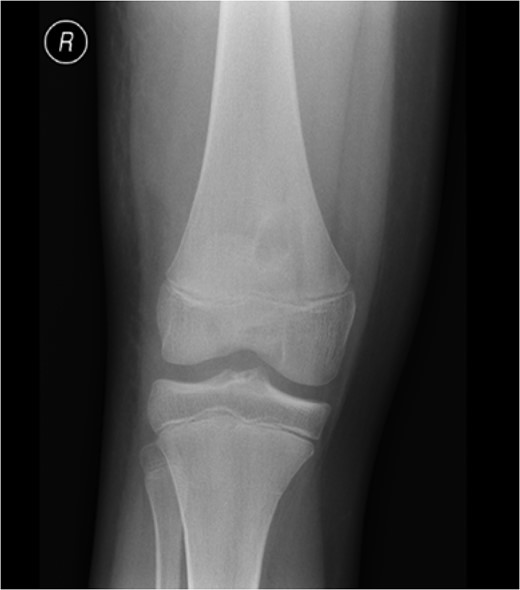

An X-ray, magnetic resonance imaging (MRI) and ultrasound scan was conducted (Fig 1, 2).

Radiograph on presentation to A + E. The radiograph displays ‘a well corticated lesion (15 mm × 17 mm) in the distal femur’.